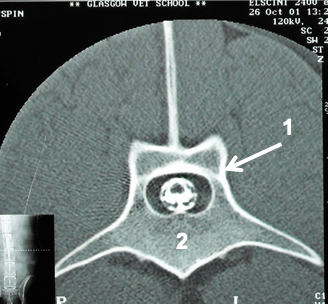

how does the vertebral foramen form

combination of the vertebral arch dorsally and the vertebral body ventrally –> forms vertebral foramen

what is the function of the vertebral foramen

route for the spinal cord to run through the bone

what structures are shown

vertebral foramen